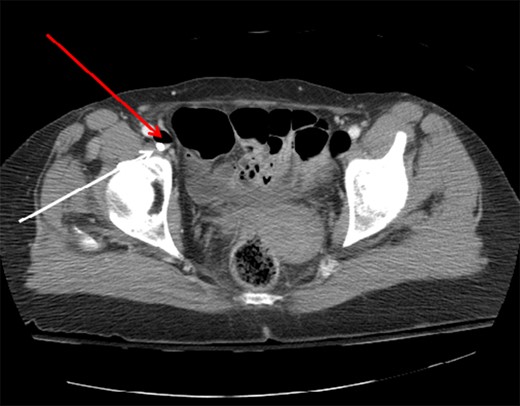

Axial CT image of the pelvis demonstrating the CVC (white arrow) with adjacent air (red arrow) in the right external iliac vein.